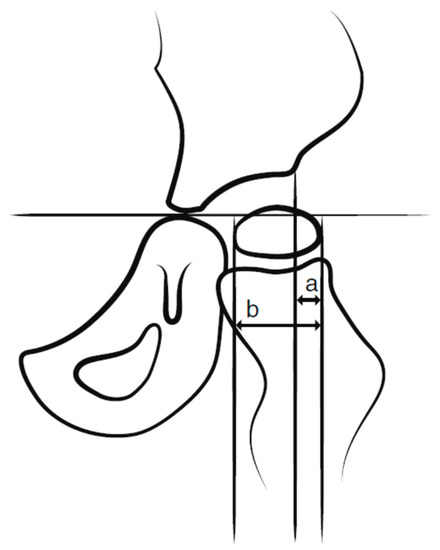

CP is one of the most common lifelong disabilities worldwide, caused by non-progressive brain damage that occurs before the age of two years [10], oftentimes already present in utero. There is great variability in functioning, however, motor function is always affected and challenges in cognition, perception, sensation, behavior, and comorbidities such as epilepsy are frequent [10,11]. Hip displacement, during which the femoral head is laterally displaced within the joint, is common in individuals with CP due to altered muscle forces across the hip joint. Hip dislocation is a severe problem with a high risk of pain, development of severe contractures, windswept deformity, and scoliosis (Figure 1), resulting in problems with posture, sitting, standing, and walking [12,13]. The risk of hip dislocation is estimated to be within 15–20% of the total population of individuals with CP and the risk is highest in those with severe limitations of gross motor function [14]. Hip dislocation in CP, though, is often preventable. Evidence demonstrates that at a population-based level, hip displacement can be prevented if young children with CP are included in surveillance and follow-up programs that include repeated radiographic and clinical examinations and preventative treatments for hip displacement [15,16]. Non-surgical management to prevent hip dislocation includes the positioning of the hip in abduction and extension when lying, sitting, and standing. Surgical treatments of hip displacement in CP, however, consist of adductor–iliopsoas lengthening (APL) or varus derotation osteotomy of the proximal femur (VDRO) and sometimes in combination with pelvic osteotomy. APL is performed primarily on younger children with a lesser degree of displacement, while osteotomy is performed on children with a more severe displacement. The results of APL may also be an indicator of how long the hip displacement was allowed to continue.

Figure 1. Pelvic radiograph of an eight-year old boy with cerebral palsy, left-sided hip dislocation, and pelvic obliquity.